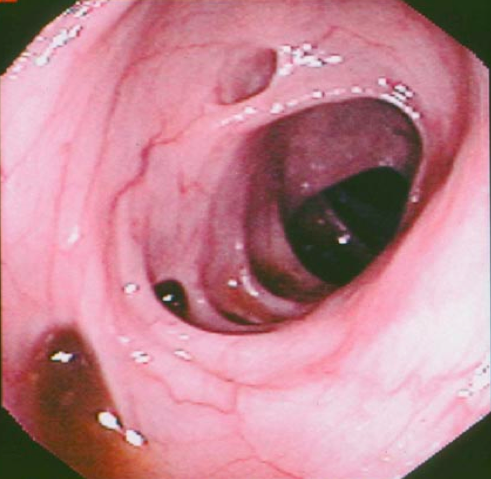

A 56-year-old journalist presented with symptoms of an acute abdomen. There was a long history of vague lower abdominal discomfort and occasional pain. He traveled frequently and often “ate on the run.” A stool sample was positive for occult blood. The WBC was 12,000 with a “shift to the left.” Endoscopy is shown below. What caused him to have this condition?

Diverticulitis is caused by increased intraluminal pressure in the colon along lines of weakness around the blood vessels that penetrate the inner muscular layer. The pressure pushes the mucosa and submucosa through the muscle wall causing a pseudodiverticulum. These then can become infected.